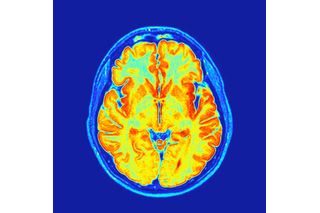

To determine how the brain responds to stimulants, researchers at the Washington University School of Medicine in St. Louis compared MRI results from 5,795 children aged 8 to 11, collected as part of the Adolescent Brain Cognitive Development (ABCD) Study. This included 337 children who had taken stimulants on the morning of the scan and a further 76 who had a prescription but had not taken medication that day. The remainder had neither been prescribed stimulants nor taken stimulants before the scan.

While the study’s authors noticed few differences between those who had taken stimulants and those who had not when it came to regions involved with attention (such as the dorsal attention network and prefrontal cortex), there were notable divergences in areas of the brain associated with reward and wakefulness. Rather than enhancing the brain’s ability to focus, the medication may work by increasing drive and boosting motivation, say researchers.

A follow-up study involving five adults without ADHD and without a history of taking prescriptive stimulants seemed to confirm these results. It was areas of the brain linked to reward and wakefulness that appeared to “light up” in response to the medication.